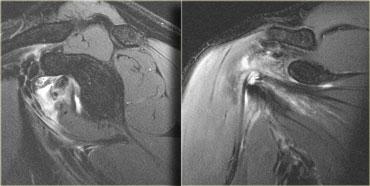

Bên trái là hình ảnh căng cơ với rách một phần cơ dưới vai.

Cơ dưới vai là cơ hội tụ (giống như cơ ngực chẳng hạn) với nhiều gân.

Phù nề sẽ có dạng phân bố đa lông chim, khi phù nề lan theo nhiều hướng dọc theo các gân khác nhau.